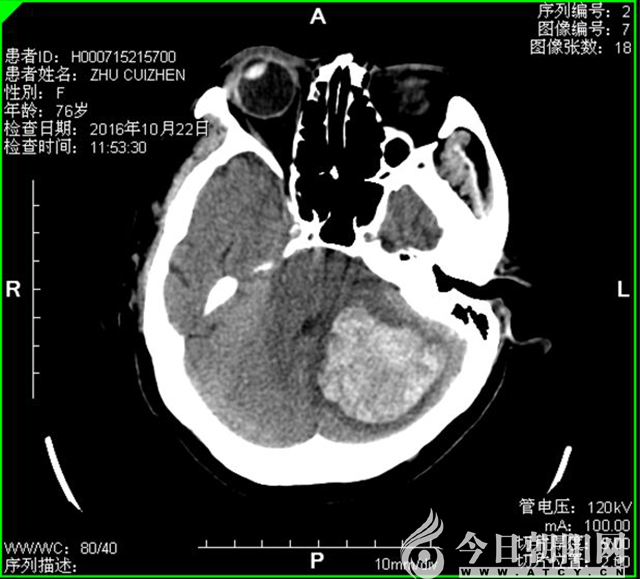

術前

患者女性,今年76歲。2016年10月22上午11點,突發(fā)劇烈頭疼,伴嘔吐咖啡色液體數(shù)次,120接診至該院急診,處于嗜睡狀態(tài),尿便失禁,呼吸急促,病情危急。該患者既往高血壓病史6年,腦梗死病史6年,糖尿病病史10年。

神經(jīng)外二科張文主任根據(jù)患者病史及顱腦CT提示,及時向患者家屬交代病情,確定手術方案。時間就是生命,有關醫(yī)護人員迅即行動,各項術前準備工作有條不紊地進行著,患者入院不到40分鐘就被接到手術室。手術順利,術中成功清除左小腦血腫約30ml。術后1天,即拔除氣管插管,患者神清,語言流利,目前轉(zhuǎn)入普通病房康復治療中。